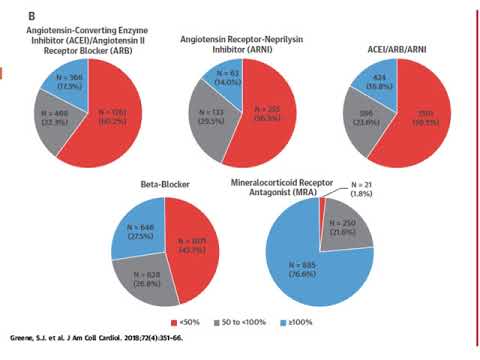

Tratamiento médico para la insuficiencia cardiaca con fracción de eyección reducida. Dra. Carolina G. Reynoso. Residencia de Cardiología. Hospital C. Argerich. Buenos Aires